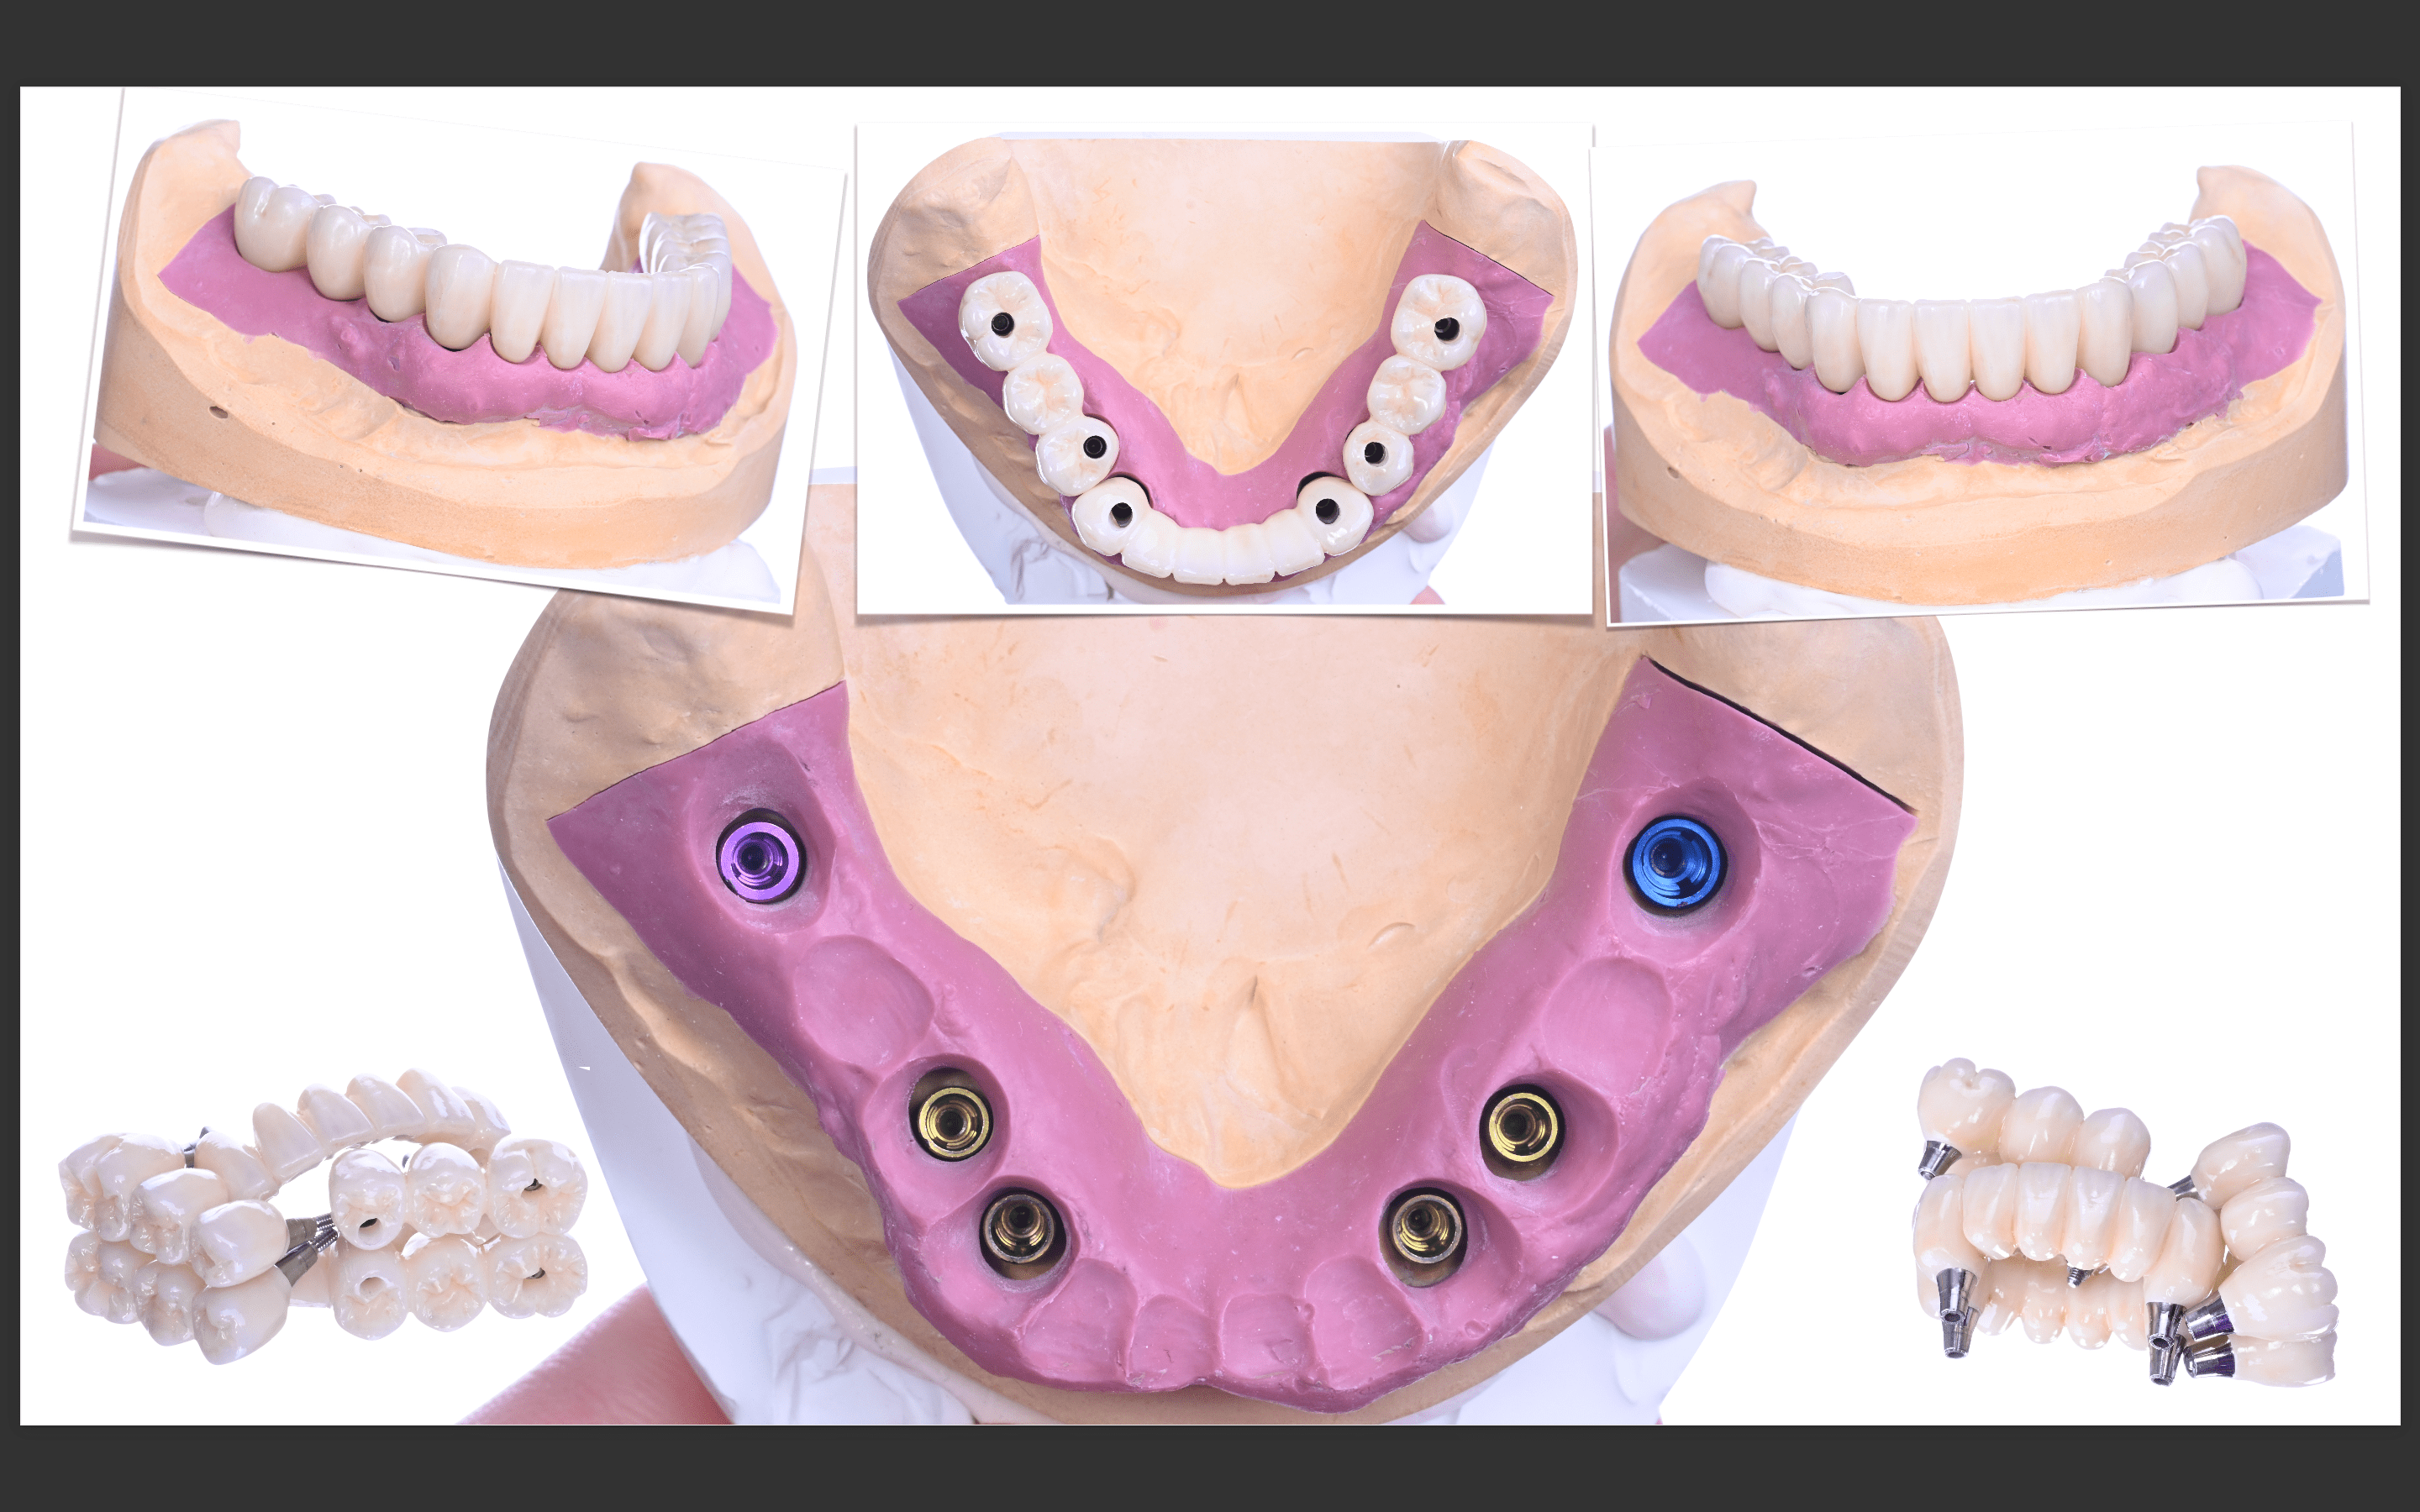

All-on-6を終えて

最終補綴

上顎:ロケーターアバットによる義歯

下顎:フルジルコニアブリッジ

治療のリスクと副作用

治療期間:約半年

治療費:¥3,850,000(税込)

リスク:インプラントのネジが緩むことはありますが、なるべく連結しないような設計にしているので、問題をはやく見つけやすくしております。